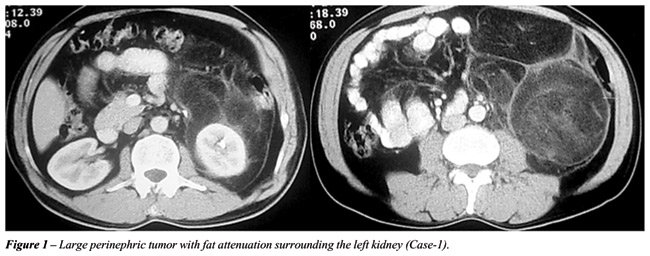

Case 1: A fifty-year diabetic and hypertensive male presented with a lump in the left side of upper abdomen and 3-month dull aching pain of. He had no history of any lower urinary tract symptoms, lithiasis or operative intervention in past. His blood sugar and blood pressure was normal with oral medication. He had normal renal function and hemogram. Computed tomography of abdomen and pelvis revealed a 12x10 centimeter mass with lipomatous density involving the perirenal fat without infiltrating surrounding organs.

Case 2: Fifty seven year old woman presented with a 2-month right flank pain with no other urinary symptoms. Clinically examination revealed right hypochondrial renal swelling. Computed tomography of abdomen and pelvis revealed 10x8 centimeter perinephric lesion with fat attenuation surrounding the upper and mid polar region.

The preoperative imaging study was suggestive of a close association of tumor with the kidneys in both the cases (Figures-1 and 2) but intraoperative assessment resulted a plan of renal sparing approach in both the situations. Intraoperatively, a well encapsulated lipomatous tumor was found to extend from the upper pole to the lower pole draping the surface of the renal capsule and infiltrating the renal capsule in one of the locations over 1 cm diameter region (Figures-3 and 4). Complete tumor resection was achieved after wedge resection of renal parenchyma with 1 cm margin.